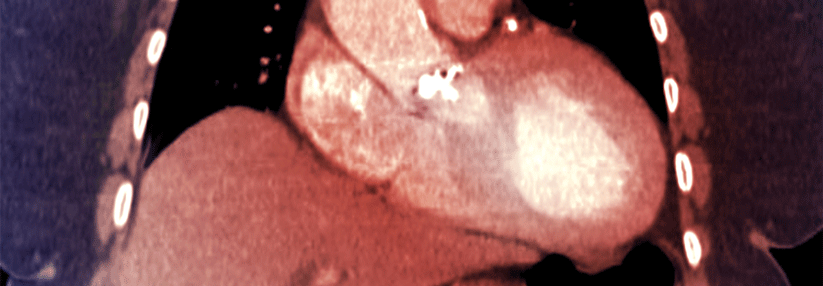

Echokardiographie

Das wichtigste diagnostische Verfahren bei Aortenstenose ist die Echokardiographie. Diese Untersuchung

• bestätigt das Vorliegen einer Aortenstenose

• erlaubt eine Einschätzung des Umfangs der Klappenverkalkung, der linkventrikulären Funktion und der Wanddicke

• deckt auf, ob weitere assoziierte Klappenerkrankungen oder pathologische Veränderungen der Aorta vorliegen

• liefert prognostische Informationen

Die Doppler-Echokardiographie ist die bevorzugte Methode zur Einschätzung des Schweregrads der Aortenstenose.

Um die Ausprägung einer Aortenstenose beurteilen zu können, sollte nicht nur die Aortenöffnungsfläche berücksichtigt werden, sondern zusätzlich folgende Parameter:

• Transvalvuläre Flussrate

• Durchschnittlicher Druckgradient

• Funktion, Größe und Wanddicke des Ventrikels

• Grad der Klappenverkalkung

• Blutdruck

• Funktioneller Status

• Low-Flow-Low-Gradient-Aortenstenose mit erhaltener Ejektionsfraktion (Aortenöffnungsfläche < 1 cm2, durchschnittlicher Druckgradient < 40 mmHg, Ejektionsfraktion ≥ 50%, SVi ≤ 35 ml/m2). Diese Kategorie ist typisch für ältere Patienten; sie geht mit einer geringen Ventrikelgröße, einer ausgeprägten linksventrikulären Hypertrophie und oft mit einer Hypertonie einher. Die Diagnose einer schweren Aortenstenose in diesem Setting stellt eine Herausforderung dar. Hilfreich ist es, den Schweregrad der Klappenverkalkung mittels Multislice-CT zu bestimmen.